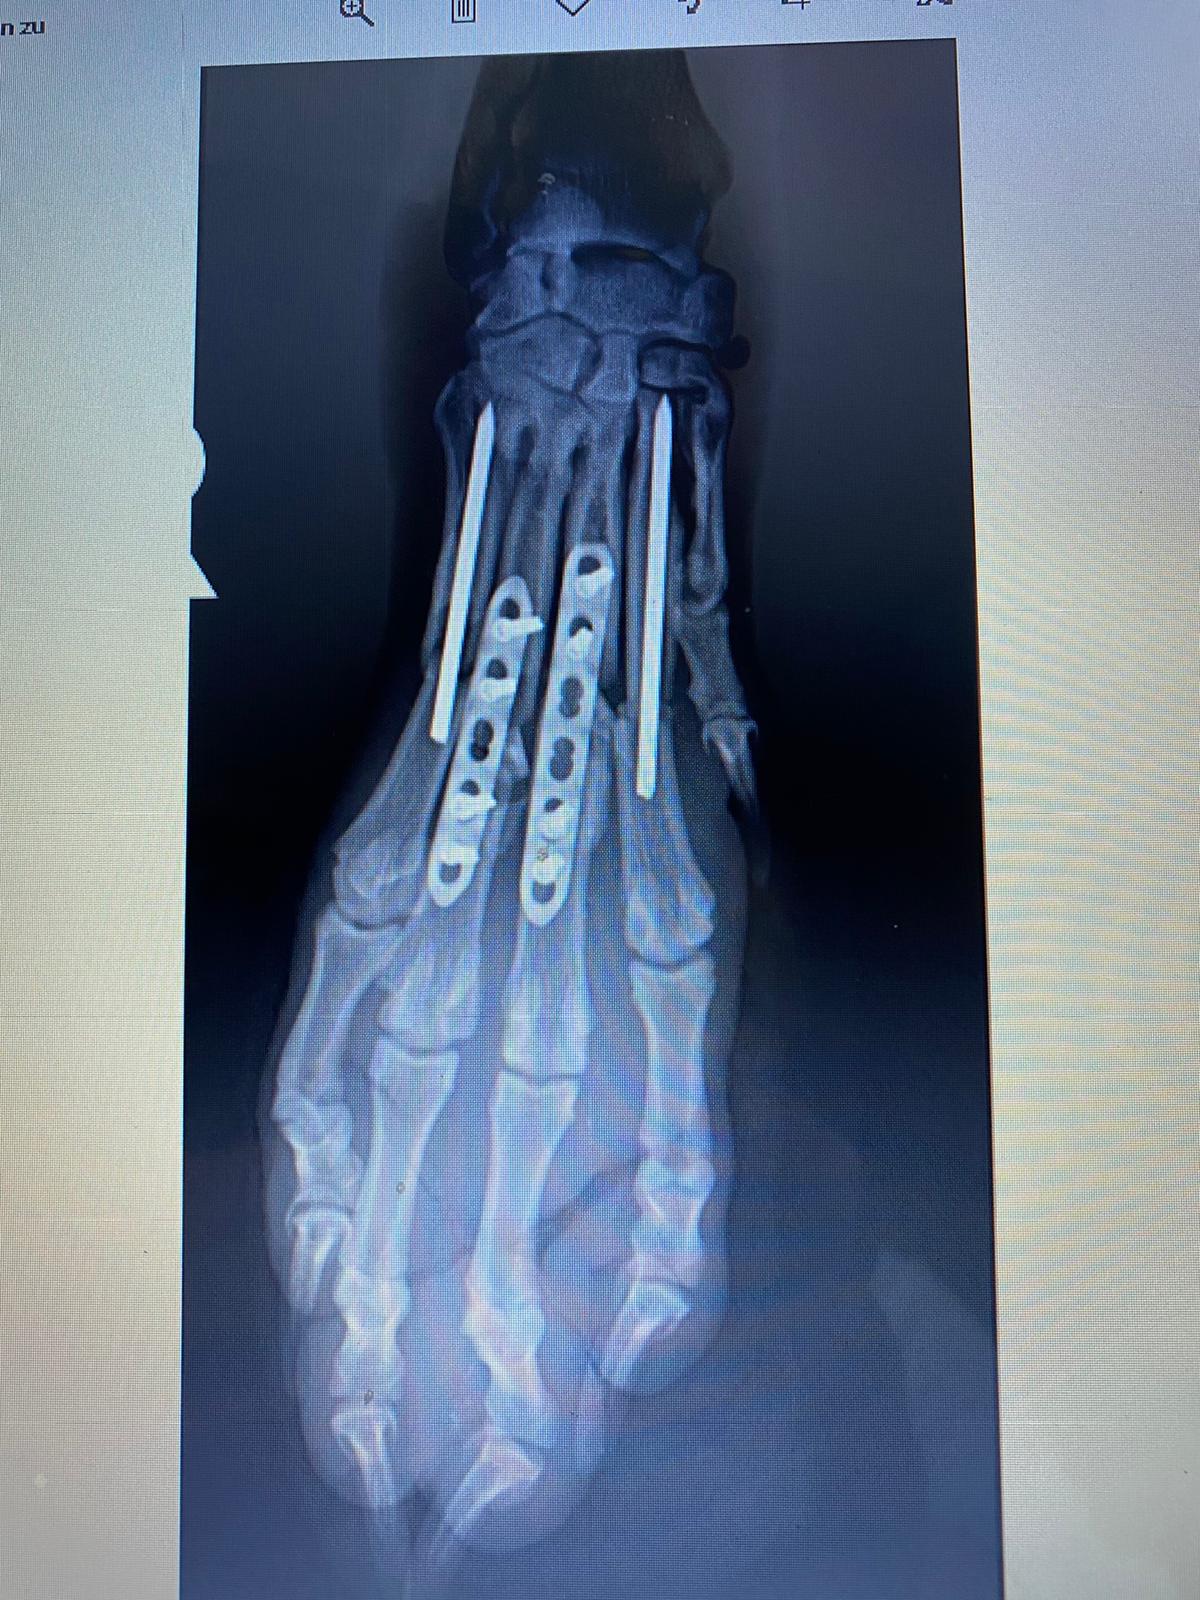

AMIR lief nach dem Schuss noch drei Kilometer weit, seine Retter hatten ihn dabei aber immer im Blick und brachten ihn schließlich direkt in eine Tierklinik, die seine schwer zertrümmerte Pfote zum Glück retten konnte.